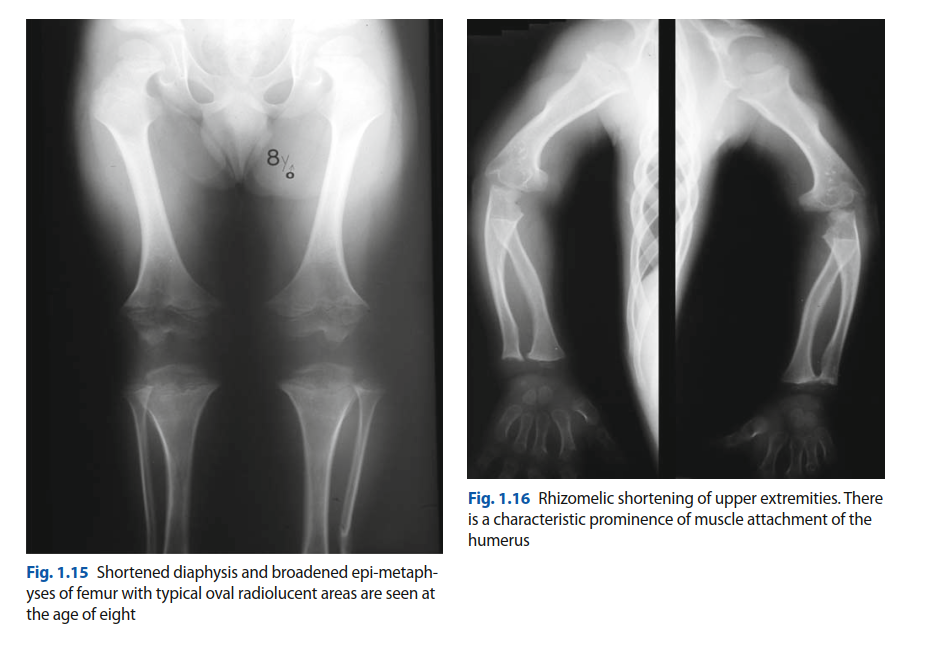

The patient carries a known diagnosis of achondroplasia, the most common form of short-limbed dwarfism, identified during infancy. Achondroplasia is an autosomal dominant genetic disorder caused by a gain-of-function mutation in the fibroblast growth factor receptor 3 gene located on chromosome 4p16.3. This mutation results in the constitutive activation of the receptor, which severely inhibits chondrocyte proliferation and differentiation within the proliferative zone of the physis. Consequently, endochondral ossification is profoundly impaired, leading to the characteristic phenotypic features of rhizomelic limb shortening, macrocephaly, frontal bossing, and midface hypoplasia.

From an orthopedic trauma perspective, the achondroplastic skeleton presents unique biomechanical and anatomic challenges. The long bones, particularly the femurs and humeri, are significantly shortened but possess a normal or increased cortical diameter, resulting in a thick, robust appearance. However, the medullary canals are typically narrow, and the metaphyseal regions exhibit excessive flaring. Furthermore, achondroplastic femurs frequently demonstrate exaggerated anterolateral bowing and altered mechanical axes, which fundamentally change the bending moments and stress distributions across the bone during traumatic loading.